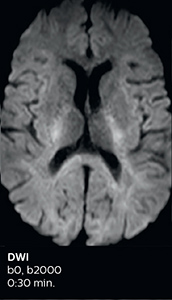

The abbreviated MS protocol for brain is only around 9 minutes, so in case of suspected multiple sclerosis, one or two more advanced sequences may be added, such as PSIR (phase sensitive inversion recovery) or susceptibility-weighted sequences to help us make more confident diagnoses in these inflammatory cases.

In this example, the optional 3D multishot susceptibility weighted sequence with 0.6 mm isotropic voxels is 2 lesions with a central vein sign (arrows) and one lesion with a phase-rim sign (arrowhead). The total scan time, including SmartBrain and axial PD/T2 3mm, is 11:10 min. and is 18:30 min. with the optional 3D PSIR and 3D SWI multishot included.

“We used to have long examination times for certain types of patients, a few lasting more than 40 minutes,” says Dr. Savatovsky. “What is remarkable, is that now all these examinations are below 30 minutes, which opens up opportunity to add more sequences when needed. It’s really hard to keep a patient for more than 40 minutes in the scanner, but because we have now cut scan times by at least 10 minutes, we can add more sequences without making the exam too long. And this is where the new system helps us make a difference. Examples include our examinations for informing brain tumor classification or giant cell arteritis workup, or for intracranial wall imaging – so in patients where we need several advanced sequences or high resolution sequences.” “We added three additional sequences in our brain neoplasm classification exam: a 3D SWI sequence, APT and ASL on top of 3D morphologic sequences, an isotropic DSC (dynamic susceptibility contrast) and multivoxel spectroscopy. I think that in patients that need a classification for brain mass, for example, we can provide a more detailed and confident diagnosis than before, allowing the clinicians to decide for either a medical workup if no tumor is suspected, or for neurosurgery as soon as possible if a neoplasm is suspected.” “In multiple sclerosis patients, we increasingly include a multishot susceptibility sequence [3] in our routine cases, thanks to the shorter scan times. Our abbreviated MS protocol for brain is around 8 to 9 minutes, so we can ask for one or two additional sequences to visualize the central veins, or to get an additional contrast to better depict posterior fossa lesions. In cases of white matter lesions of unknown significance on FLAIR images, for example when we see high signal hyperintensities in the brain, we can add on more advanced sequences such as PSIR (phase sensitive inversion recovery) or susceptibility-weighted sequences to help us in distinguishing between MS and nonspecific or vascular abnormalities in these inflammatory cases.”